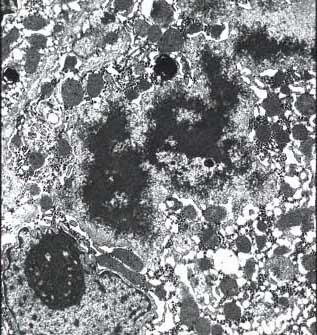

li-8-4-15.jpg (39589 bytes)

Fig. 8-4-15:

Mallory bodies